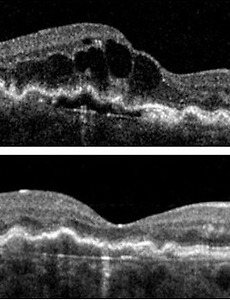

병적 고도근시와 후포도종(posterior staphyloma), 중심와 분리증(myopic foveoschisis), 근시성 황반원공(myopic macular hole) 눈의 도수로는 -6 디옵터의 굴절력, 안구의 길이로는 26 mm 의 안축장을 넘는 심한 고도근시에서, 시력 장애를 유발할수 있는 이차적인 안저 변화가 동반된 경우를 병적인 고도근시 (pathologic high myopia)라고 합니다. 이러한 병적 고도근시는, 성장과정에서 발생한 일반적인 고도근시와는 달리, 눈의 도수는 점점 나빠지고, 안축장의 길이 역시 점점 나빠지는것이 특징입니다. 이러한 병적 고도근시에서 가장 중요한 소견은, 안구에서 가장 질긴 조직이자, 안구의 형태를 유지해주는 가장 중요한 조직인 공막(sclera)조직이 늘어나고, 약해지는 것입니다. 이를 안구조직이 포도송이 처럼 늘어난다고 하여, 안구 포도종 (staphyloma)이라고 하며, 특히 안구의 뒤편이 늘어나기 때문에, 이를 안구 .. 2018. 6. 24.